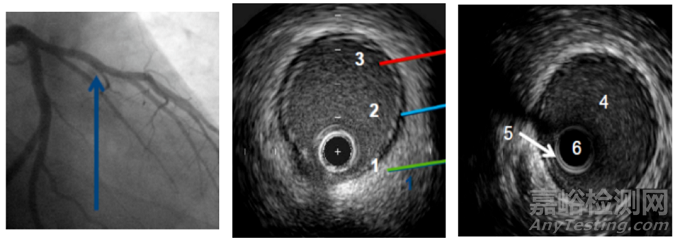

▲血管在超聲下的圖像

1: 外膜是由膠原蛋白組成,超聲反射信號(hào)強(qiáng)烈(顯示為白色)

2: 中膜是由平滑肌細(xì)胞組成,無超聲回波信號(hào)(顯示為灰色)

3: 內(nèi)膜致密,介于中膜和血流之間,顯示為白色

4.管腔:血液

5.衰蕩區(qū):“光暈”

6.盲區(qū):導(dǎo)管